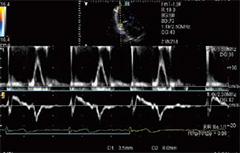

Çift Geçitli Doppler

Aynı kalp devri süresince iki farklı lokasyondan Doppler dalga formlarının gözlemlenmesine olanak verir. Kan akışı ve Doku Doppler dalga formları, atımdan atıma varyasyondan kaçınarak LV diyastolik performans göstergesi, E/e’ oranı gibi ölçümlere olanak vermektedir. İki farklı dalga formundan gelen basit ölçümler fetal aritmide de faydalı olabilir.